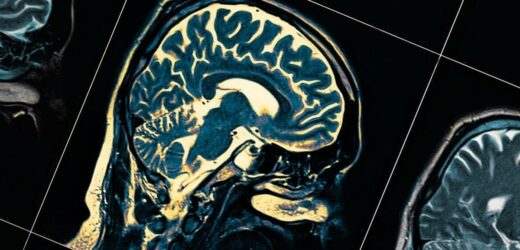

There is a subtype of cells in the part of the brain called the substantia nigra that die when people have Parkinson’s disease. The cells make a signalling chemical, dopamine, which is involved with controlling movement. While a number of treatments for Parkinson’s are able to boost dopamine levels, researchers have stressed that better treatments are needed as the effectiveness of existing ones tend to diminish over time.

The experts studied cells with 15,000 nuclei from the substantia nigra of eight people without the disease who had donated their brains after death.

This uncovered that there are 10 different subtypes of dopamine-producing cells in this part of the brain.

The researchers then used the same technique on 10 brains belonging to people who had Parkinson’s or a similar condition known as Lewy body dementia when they died.

The discovered that only one of the subtypes of brain cells was reduced, indicating this subtype died while those people were still alive.